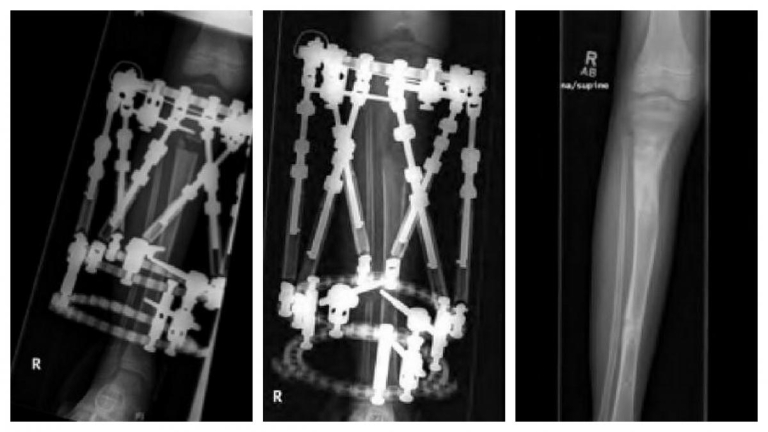

S.D. is a 2-year-old female who presented to the Orthopaedic Center at Dayton Children’s for an LLI noticed by the family. Her birth and developmental history were unremarkable and there was no family history of limb deformity. Examination revealed an LLI by tape measure and blocks of 2.5 cm left longer than right. She had hyperpigmentation involving her trunk, abdomen and left leg. Her neurovascular exam was normal, and she had hemi-hyper-trophy on her left calf with 2.5 cm increase in growth compared to the contralateral leg. A scanogram was obtained which showed a 3 cm overall limb length inequality with 2.0 cm difference in the tibias. Genetics was consulted verifying diagnosis of Klippel-Trenaunay-Weber syndrome. MRI of her brain and cervical, thoracic lumbar spine revealed no abnormalities. By age 6, her exam revealed a progressive discrepancy showing a 7.0 cm LLI; thus she had her first limb lengthening using a spatial frame external fixator and obtaining 5 cm of length, 20 percent of the length of her tibia (Figure 6).

During her lengthening of the tibia, she developed an equinus contracture on the lengthened leg requiring a percutaneous heel cord lengthening upon removal of the frame.